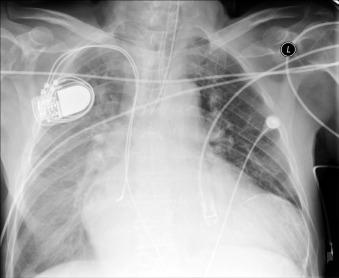

Pericardial calcification ( Figs. 27-1 to 27-4 ) is most prominent in the interventricular and atrioventricular grooves, and lateral to the right atrial and ventricular walls ( Graphic 27-1 ). When looking for pericardial calcification, it is necessary to scrutinize the lateral chest radiograph well, particularly the diaphragmatic surface. Pericardial calcification does not usually involve the left heart as much the right heart, and it does not often involve the apex (which, if calcified, is far more often due to prior infarction). Pericardial calcification should prompt serious consideration of the diagnosis of constrictive pericarditis, and clinicians should seek other radiographic and clinical features of constriction.

A calcified ventricular aneurysm is seen as a fine dense line when viewed on edge and is consistent with an old transmural infarction. On the frontal chest radiograph, an anterolateral, or apical, calcified aneurysm may be visible. Rarely, a calcified septal aneurysm may be seen on a lateral chest radiograph. Myocardium may calcify following traumatic injury as well as postinfarction.